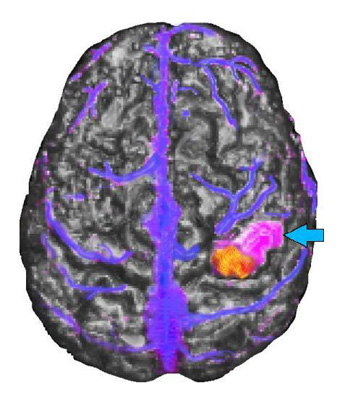

15 year-old right handed girl with sensory-motor partial seizures involving the left hand since the age of 5. MRI showed a focal signal abnormality in the right postcentral gyrus consistent with a developmental tumor without changes over 2 years.

MRI of the brain appears in gray scale, functional MR activation is in yellow and red, the tumor is purple (light blue arrow), and the veins are blue. The tumor appears located in the post-central gyrus lateral and rostral to the functional activation. The relationship between the tumor and the functional activation was confirmed during awake intraoperative mapping. The venous landmarks provided useful information to the operating surgeon. The patient's tumor was removed without residual monoplegia. The patient had only transient loss of stereognosis and proprioception involving the 3rd, 4th, and 5th fingers, post-operatively.